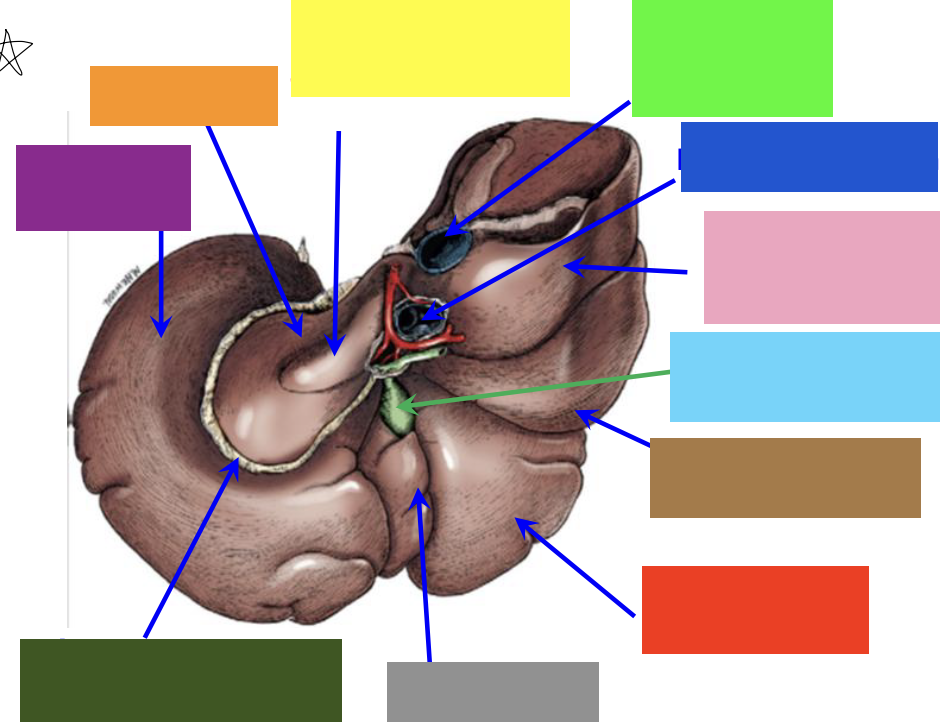

purple box

left lateral lobe

orange box

caudate lobe

yellow box

papillary process of the caudate lobe

neon green box

right lateral lobe

dark blue box

hepatic portal vein

pink box

caudate process of the caudate lobe

light blue box

gall bladder

brown box

right lateral lobe

red box

right medial lobe

grey box

quadrate lobe

dark green box

lesser omentum